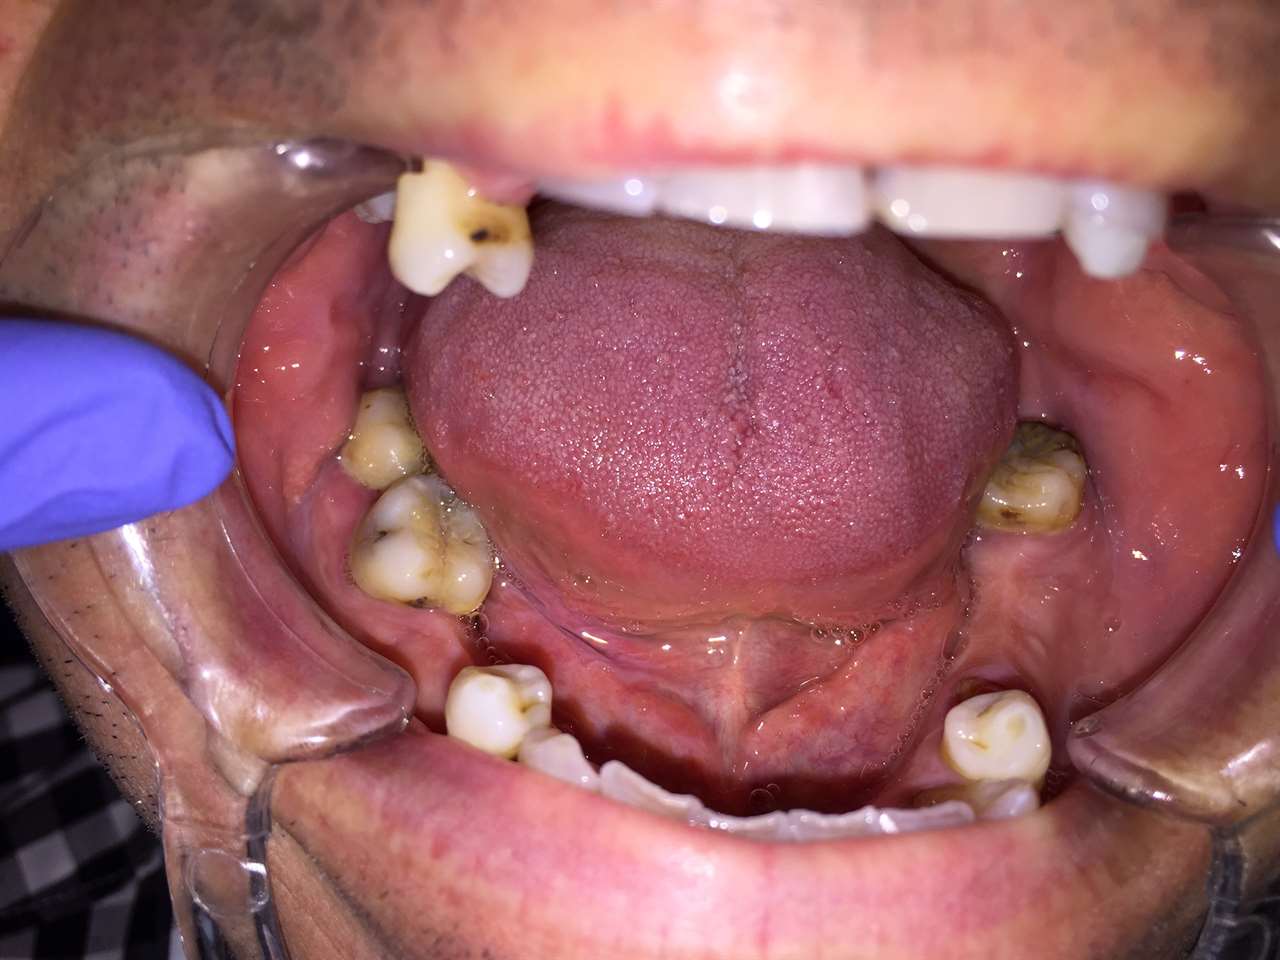

Alsó állcsont teljes rehabilitációja 72 óra alatt, azonnal terhelhető implantátumokkal súlyos paradontitisben szenvedő dohányzó páciens esetében. Az alsó állcsont fogai mind mozogtak az előrehaladott fogágypusztulás miatt.

A fogakat eltávolítottuk, a gyulladt, fertőzött csontot kitakarítottuk, kifertőtlenítettük, majd azonnal implantáltunk.

Svájci, IHDE márkájú, azonnal terhelhető implantátumokat helyzetünk be, és ezekre harmadnapra rögzített, hosszútávú, fémvázas, esztétikus műanyaggal leplezett hidat ragasztottunk be.

Ezt az ideiglenes hidat a sebek gyógyulása miatt használjuk, de tartóssága miatt véglegesként is használható.

A legtöbb esetben, ahogy itt is, 6 hónap múlva porcelán hídra cseréljük, a teljes gyógyulás után.